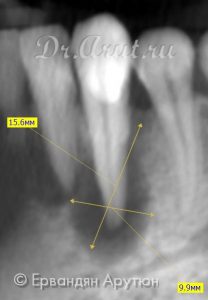

Объективно: Подвижность зубов 32 и 33 I степени. Свищ на вестибулярной поверхности между 33 и 34 зубами. Перкуссия 33 зуба безболезненная, термометрия безболезненная. На вестибулярно-дистальной поверхности пломба. ЭОД выше 200 μА. 32 интактный. ЭОД 6 μА. Термометрия болезненная, боль проходит сразу, перкуссия безболезненная. На компьютерной томограмме очаг просветления в области 33 и 32 зубов (периапикальный абсцесс) размером 16×16×6 мм. В анамнезе отсутствовали жалобы на боль в 33 зубе. После трепанации 33 зуба и инструментальной обработки корневого канала произошло обильного выделение гноя.

Через 3 месяца (апрель 2018) пациент также не предъявлял жалоб. Была произведена инструментальная и медикаментозная обработка корневого канала (3% гипохлоритом натрия и 3% перекисью водорода). Канал запломбирован AH plus с гуттаперчевым штифтом методом вертикальной конденсации. На момент пломбирования оставался небольшой очаг просветления в области верхушки корня 33 зуба. Остальная часть костной ткани восстановилась, в том числе и периодонт.